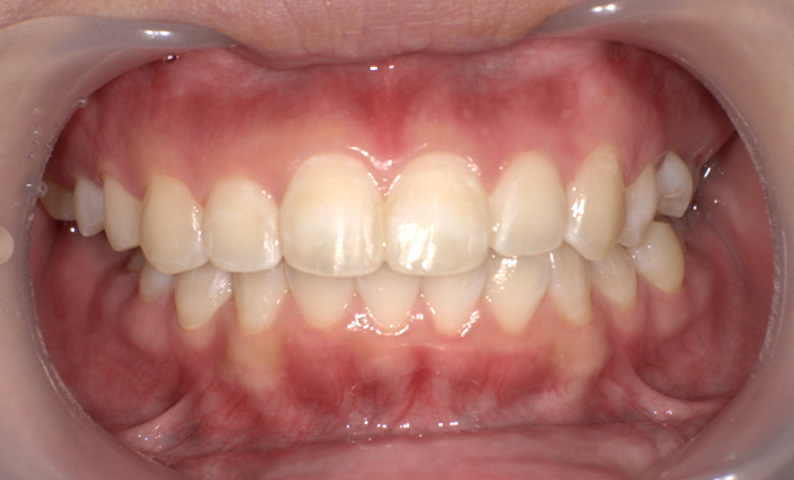

症例_011 「出っ歯」症例

治療期間:7ヶ月金額:30万円+税20代女性出っ歯捻転歯上の前歯だけ

| Before | After |